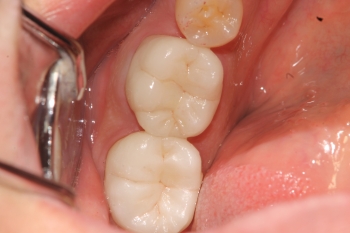

症例写真 セラミック治療前後

当医院での奥歯のセラミック治療は従来のセラミックより強度のあるジルコニアでおこないます。

写真(形成中)のように歯茎をよけながら凸凹してないか、

マイクロスコープで丁寧に確認していきます。